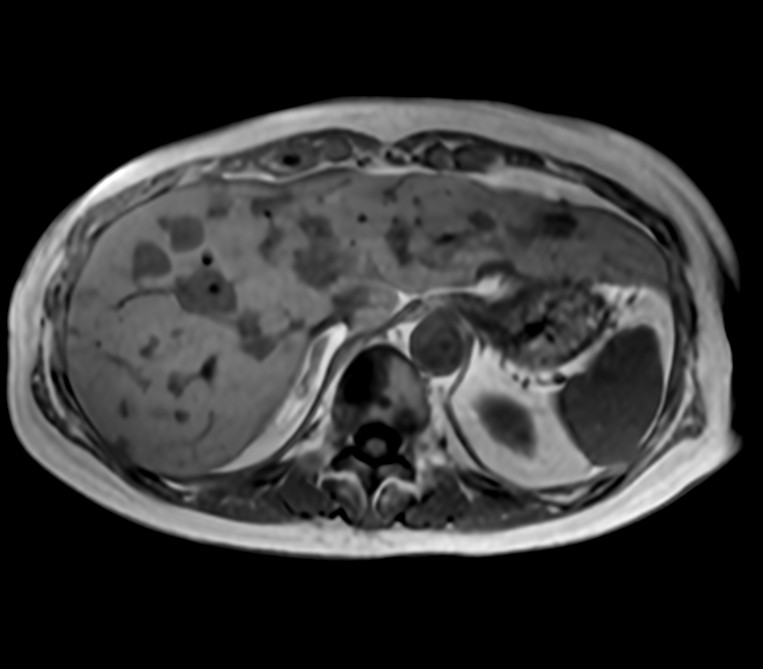

Axial T1w FFE (In Phase)